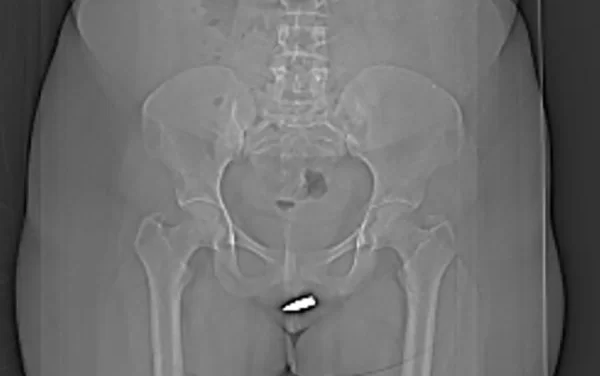

A jovem foi levada às pressas para o Hospital Erdoğan, na capital do país, queixando-se de fortes dores na vagina. Exames de tomografia computadorizada mostraram que o projétil de 2 centímetros atravessou a vulva da paciente e ficou alojado dentro do clitóris dela.

O projétil foi removido cirurgicamente sob anestesia local. Os médicos destacaram que o procedimento precisou ser feito com cuidado extra para não danificar a uretra e a região pélvica da paciente. A jovem teve alta no dia seguinte, depois de uma avaliação médica constatar que ela não sofreu complicações devido à bala.